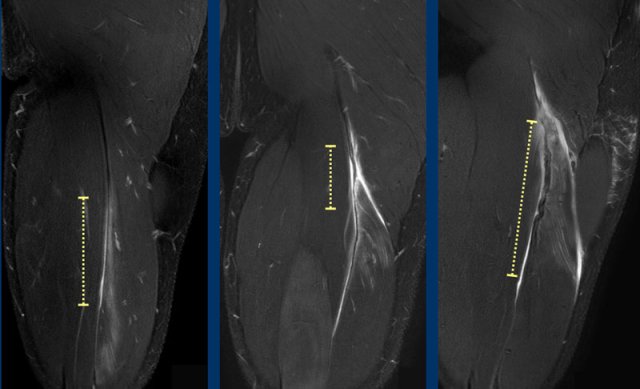

Total length of the edema is noted (white dotted line). Now take a closer look at the tendon (yellow dotted line) and continue reading.

Length of tendon distortion

When the tendon looks normal, straining is probable low grade.

Tendon thickening, tendon waviness, high signal of the tendon can all be signs of higher grade straining.

Case 1: normal tendon.

Case 2 slightly thickening and wavy aspect of a short length of the tendon.

Case 3: obvious thickening and waviness

All these signs have to be described in your report.

Total length of the distorted tendon is noted.

In this case, biceps femoris tendon injury was classified as grade 3 partial injury, since the length of the edema is > 15cm (white dotted line) and the length of the distorted tendon is > 5cm (yellow dotted line).

Two more cases to demonstrate this classification.

A muscle edema 5-10cm (white dotted line) present at the MTJ without architectural distortion of the tendon, classified as BAMIC 2b.

B muscle edema >15cm (white dotted line), at the MTJ / intramuscular tendon, tendon distortion > 5cm (yellow dotted line). The tendon shows disruption with loss of low signal intensity within the tendon along with a wavy appearance indicating focal loss of tension. BAMIC 3b/c.